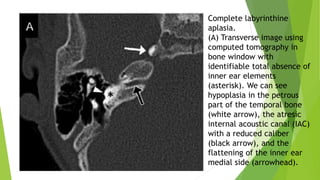

Complete labyrinthine

aplasia.

(A) Transverse image using

computed tomography in

bone window with

identifiable total absence of

inner ear elements

(asterisk). We can see

hypoplasia in the petrous

part of the temporal bone

(white arrow), the atresic

internal acoustic canal (IAC)

with a reduced caliber

(black arrow), and the

flattening of the inner ear

medial side (arrowhead).